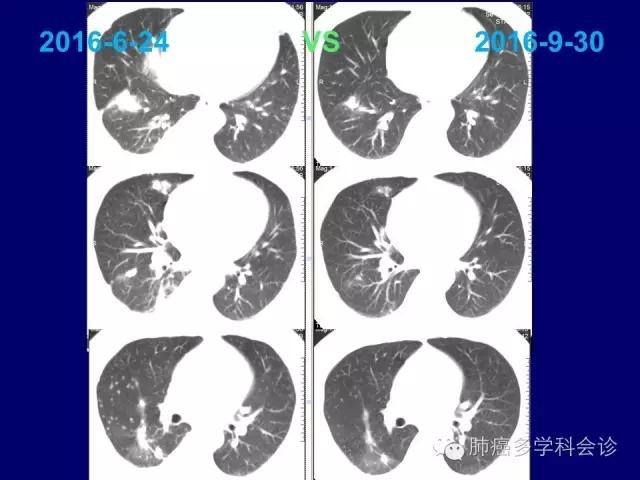

对PEM为基础的化疗敏感

化疗耐药后再使用ALK抑制剂,会明显推迟后者耐药的形成,充分发挥化疗和靶向治疗各自潜能和“相加”(?)作用。41.jpg